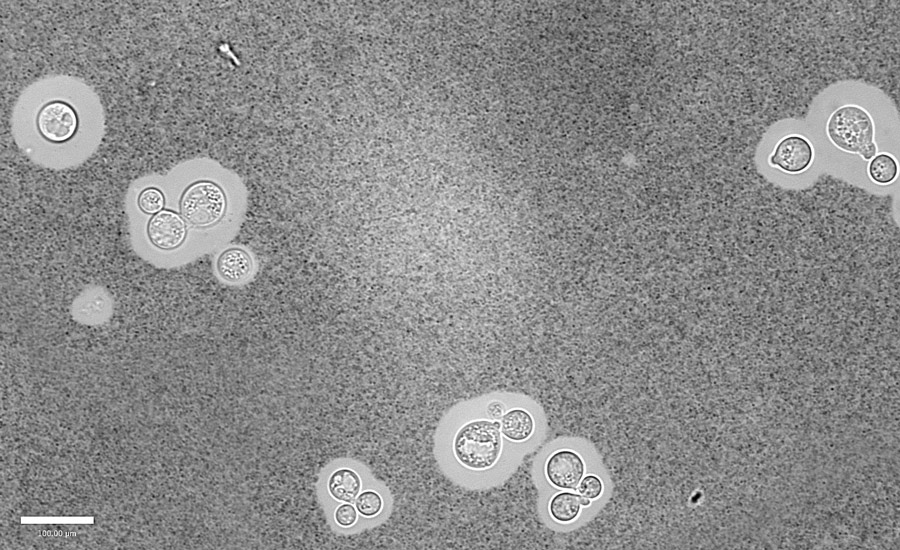

行动中蛋白质组学的一个有趣的例子是人类真菌病原体的表征Cryptococcus neoformans.,这在免疫功能低下的个体中最常与感染有关。从历史上看,研究c . neoformans依赖于更成熟的技术,比如基因组分析。然而,质谱分析和生物信息学工具和数据库的最新进展为了解真菌在感染过程中使用的生物过程提供了更多的机会,如蛋白质的释放或分泌。蛋白质组学还提供了对疾病至关重要的调节机制的见解。

鉴于抗真菌菌株的产生不断增长c . neoformans,了解更多关于响应独特环境的蛋白质的更多信息为开发替代治疗路线铺平了道路。Geddes-Mcalister博士最近曾描述过准备的有用方法c . neoformans样品和设计方案用于蛋白质组的分析变化。这提供了未来研究的基础,进一步接受这项工作,一天导致更深入地了解如何以及为什么在整个真菌感染过程中的改变。